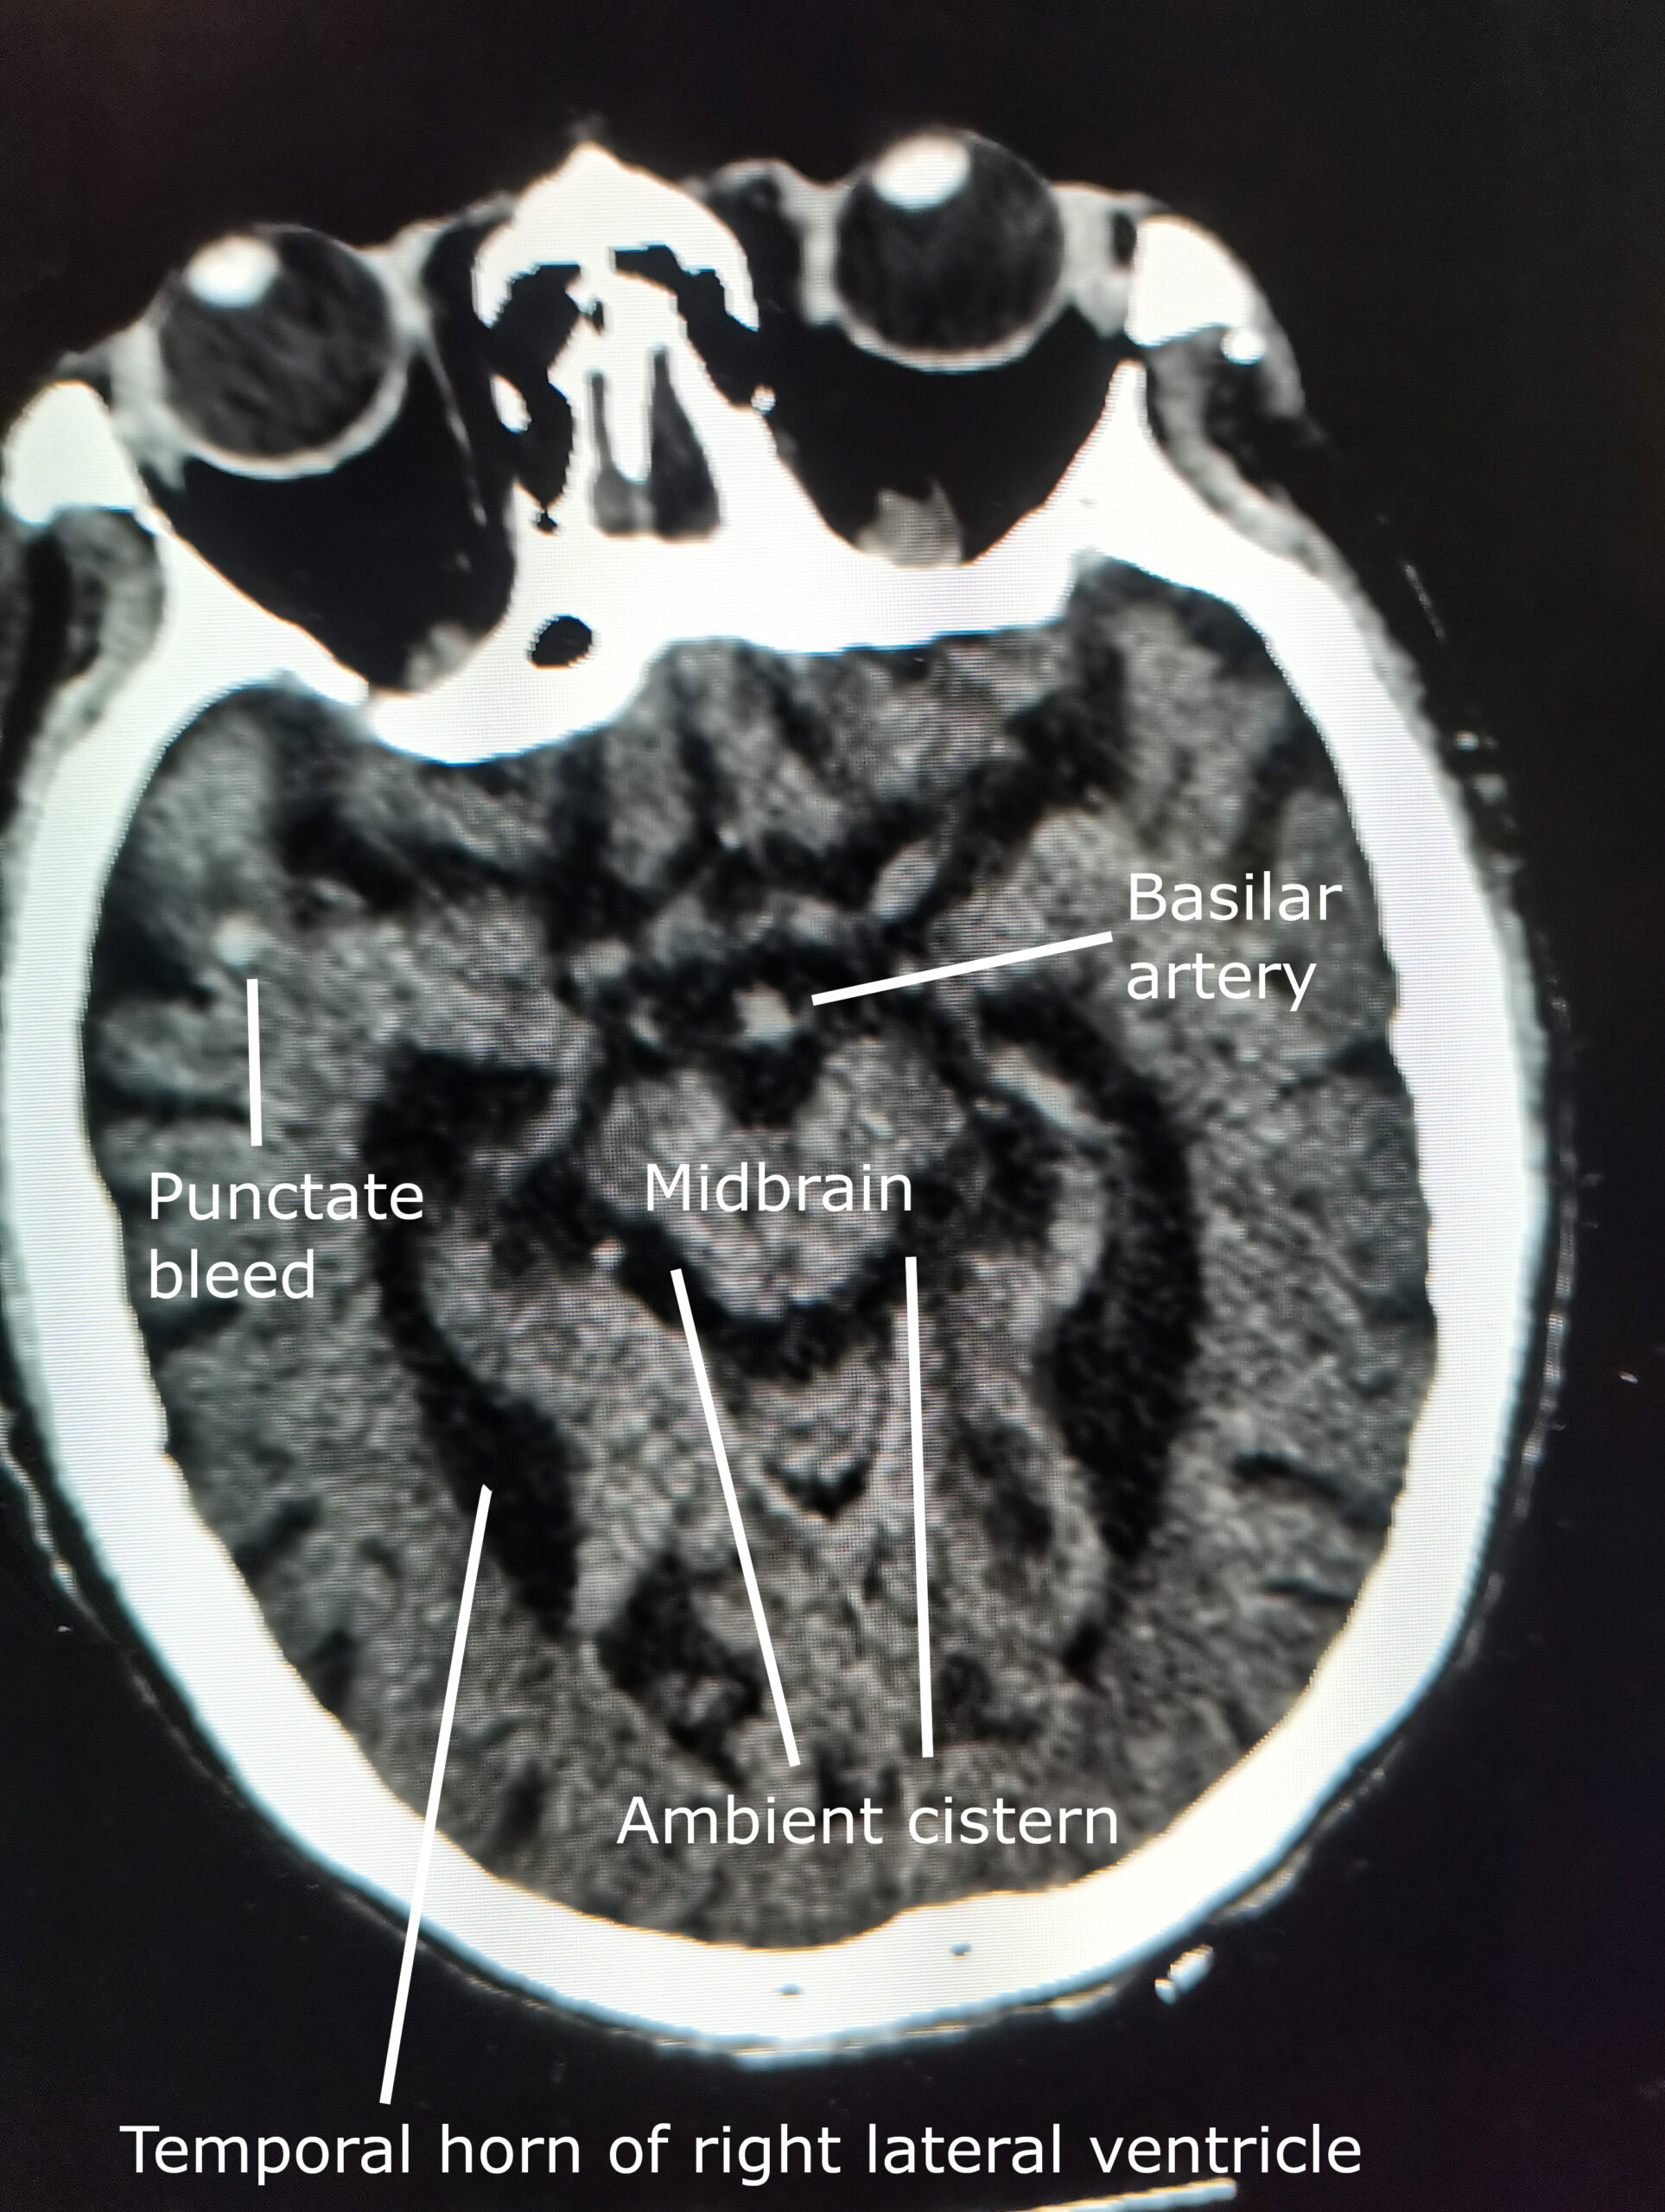

Chapter 1 Introduction to Pathophysiology; Cellular Responses to Stress, Injury, and Aging